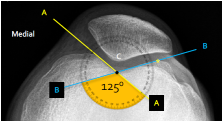

Q what is the name of this measurement? and what is the average + range?

A: Sulcus Angle

assesses the depth of the intercondylar groove. The average is 138°, with a range of 132-144°.